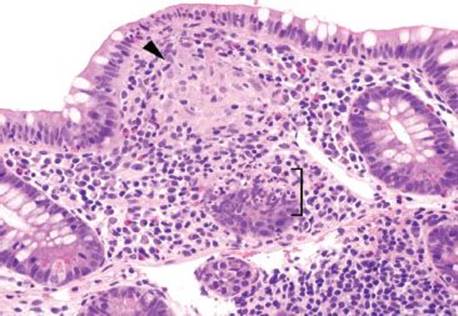

Figure 3.53 Acute ileitis pattern, aphthoid lesion. Higher power of previous case. An aphthoid lesion/ulcer refers to acute inflammation in the epithelium overlying a lymphoid aggregate. In the appropriate clinicopathologic context, an aphthoid lesion can lend support to the diagnosis of Crohn disease.

Figure 3.54 Acute ileitis pattern. A pocket of luminal neutrophils is seen (bracket) along with acute inflammation in the epithelium (arrowheads).

When assessing the acute ileitis pattern, it is worthwhile to carefully scrutinize the background mucosa for any additional diagnostic clues that might help refine the diagnosis. For example, aphthoid lesions/ulcers consist of acute inflammation in the epithelium overlying lymphoid aggregates and their presence can lend support to a clinicopathologic diagnosis of Crohn disease (Figs. 3.52–3.54). Although granulomata can be difficult to detect in the normally busy-appearing terminal ileum biopsies, their presence can also be helpful when considering the possibility of Crohn disease, infection, sarcoidosis, or medication injury (Figs. 3.58–3.65). Features of chronic mucosal injury are also important to identify, such as pyloric gland metaplasia and architectural distortion, although these features can be seen with chronic injury of any sort, such as chronic NSAID-associated injury or chronic infections (Figs. 3.58–3.73). Histologic features of chronic mucosal injury are extensively discussed in Chronic Colitis, Colon Chapter. Based on the overlapping features between IBD, chronic medication injury, and chronic infection, IBD is remains a clinicopathologic diagnosis that must encompass all available clinicopathologic features (clinical symptomatology, disease course, disease distribution pattern, pertinent microbiologic studies, and family history, etc.).13